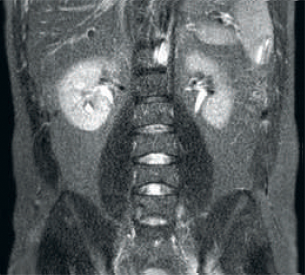

Resultado: imagens com ruído usando parâmetros idênticos de varredura

Maior consistência e qualidade de imagem aprimorada A tecnologia RF dStream receptora digitaliza o sinal de RM diretamente na bobina de RF, resultando em um aumento da SNR de até 40% ao longo de todo o volume de imagem. Fluxo de trabalho simplificado e produtividade aprimorada A bobina posterior integrada ao tampo da mesa elimina o manejo da bobina em 60% dos exames. A leveza da conformação das bobinas anteriores e as conexões da bobina em um cabo único que pode ser manejado com uma só mão aumentam a facilidade operacional.